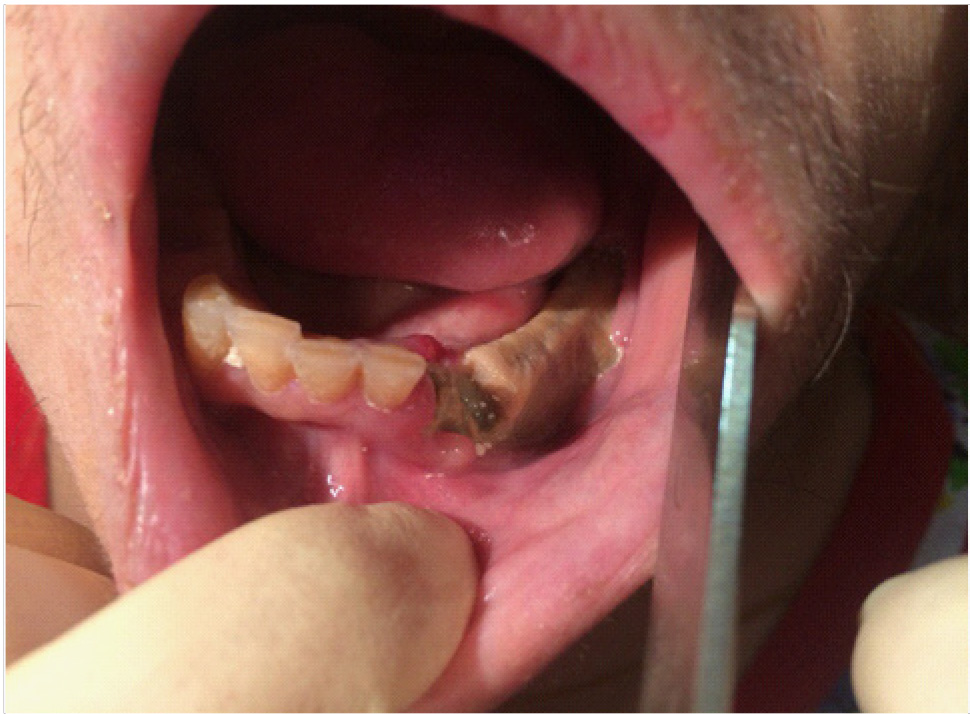

Объективные данные обследования. Общее состояние на момент осмотра удовлетворительное. Конфигурация лица изменена за счет послеоперационных явлений. Определяется послеоперационная рана с гнойно-воспалительными явлениями. Определяются явления лучевого остеонекроза нижней челюсти справа (рис. 9–11). Открывание рта ограничено, умеренно болезненное. Лечение на амбулаторном этапе заключалось в активной санации гнойно-некротических проявлений в раневой поверхности, активное орошение антисептическими растворами, протеолитическими ферментами. Активная антибактериальная, противовоспалительная, симптоматическая терапия.

Рис. 9. Клинические проявления лучевого остеонекроза нижней челюсти справа

Рис. 10. Клинические проявления лучевого остеонекроза нижней челюсти справа на этапе лечения

Рис. 11. Клинические проявления лучевого остеонекроза нижней челюсти с развитием патологического перелома нижней челюсти справа

На 10-е сутки от начала лечения пациента на амбулаторном этапе на фоне снижения гнойно-некротических явлений в ране пациент обратился к врачу – стоматологу-хирургу с жалобами на патологическую подвижность нижней челюсти справа в проекции очага лучевого остеонекроза. При осмотре диагностирован патологический перелом нижней челюсти справа, пациент госпитализирован в отделение челюстно-лицевой хирургии для дальнейшего лечения.